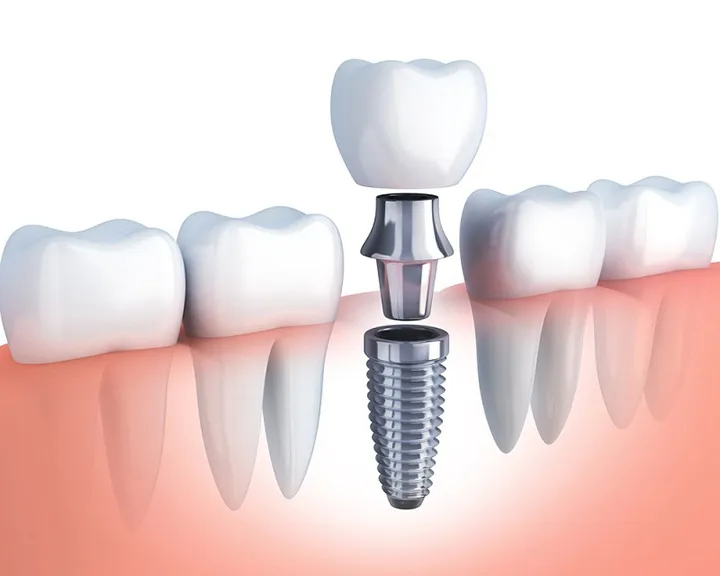

Bọc răng sứ

Bọc răng sứ là phương pháp điều trị các kiểu răng hô không cần niềng. Nó thường được áp dụng cho các trường hợp hô nhẹ. Phương pháp này bao gồm việc mài bớt một phần men răng. Sau đó ốp lên một lớp sứ đã được chế tác để khắc phục tình trạng răng hô. Răng sứ có màu sắc và hình dáng tự nhiên. Từ đó giúp mang lại một nụ cười thẩm mỹ và hài hòa hơn.

Tuy nhiên, đây không phải là phương pháp tối ưu cho tất cả các trường hợp. Đặc biệt là đối với các tình trạng răng hô nặng. Việc mài răng quá mức có thể gây tổn thương đến cấu trúc răng thật. Từ đó khiến răng dễ bị nứt, vỡ hoặc hư hại theo thời gian. Vì vậy, phương pháp này chỉ nên được áp dụng cho các trường hợp răng hô nhẹ. Đồng thời khi thực hiện cần có sự tư vấn kỹ lưỡng từ bác sĩ nha khoa.